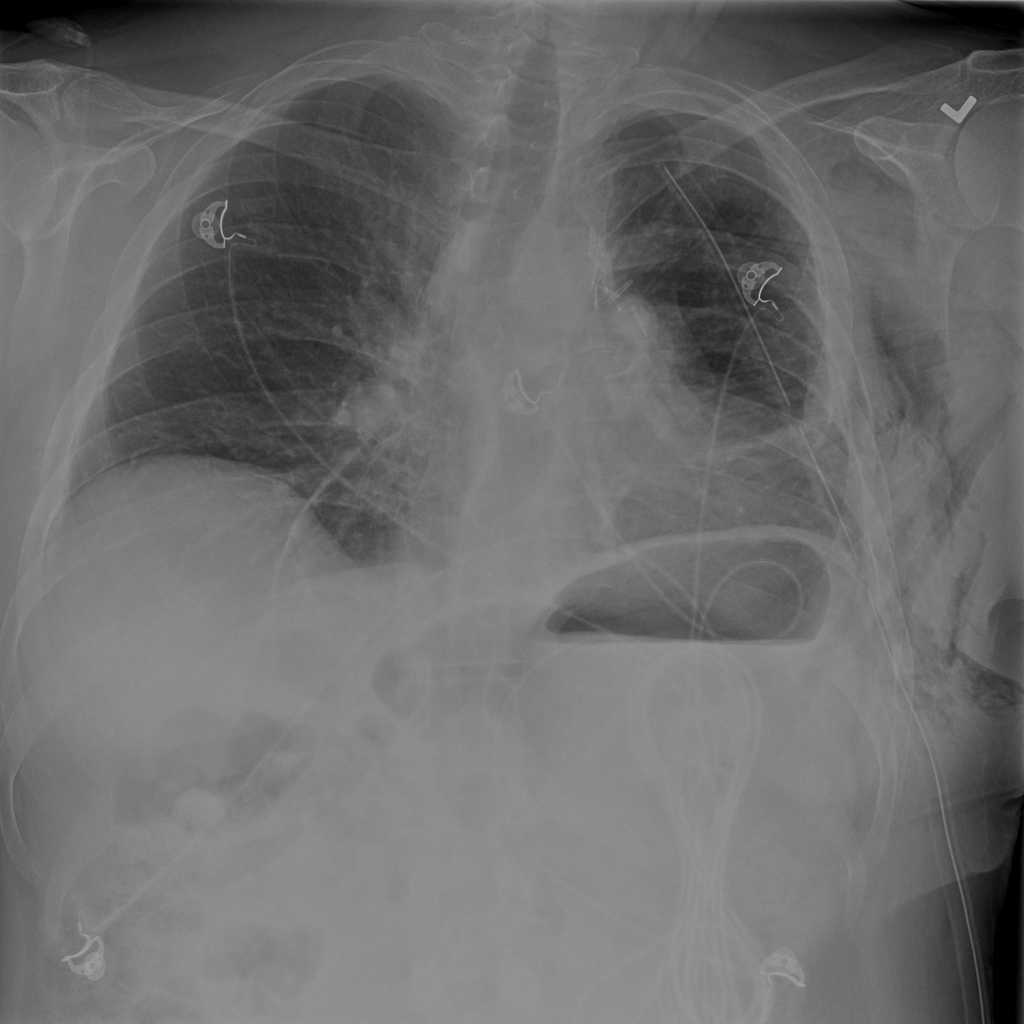

PAT-C255 · IMG-000Emphysema

PAT-C255 · IMG-000

PA